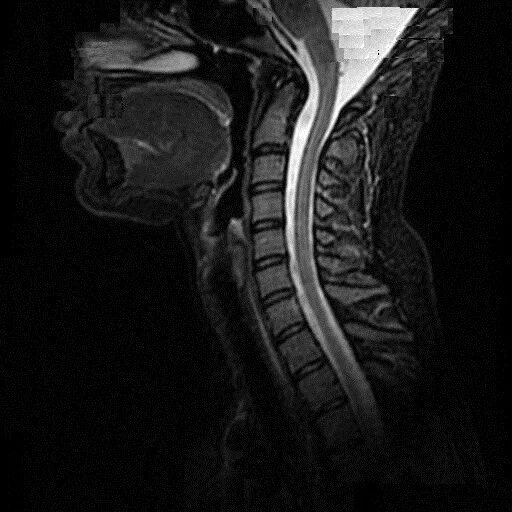

Сколько по времени делается мрт шейного отдела